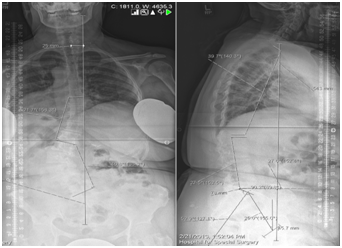

- Reduced normal dorsal kyphosis (Figure 1).

Figure 1 Compensation (Lumbar Kyphosis )à Decrease in S S ↑ Increase in PT, Hip Extension, Knee bend , Decrease in thoracic curve.

- Psychological assessment of elderly is very valuable before major surgery (Figure 5,6).

Figure 5 Whole spine x ray films in coronal and sagittal planes.